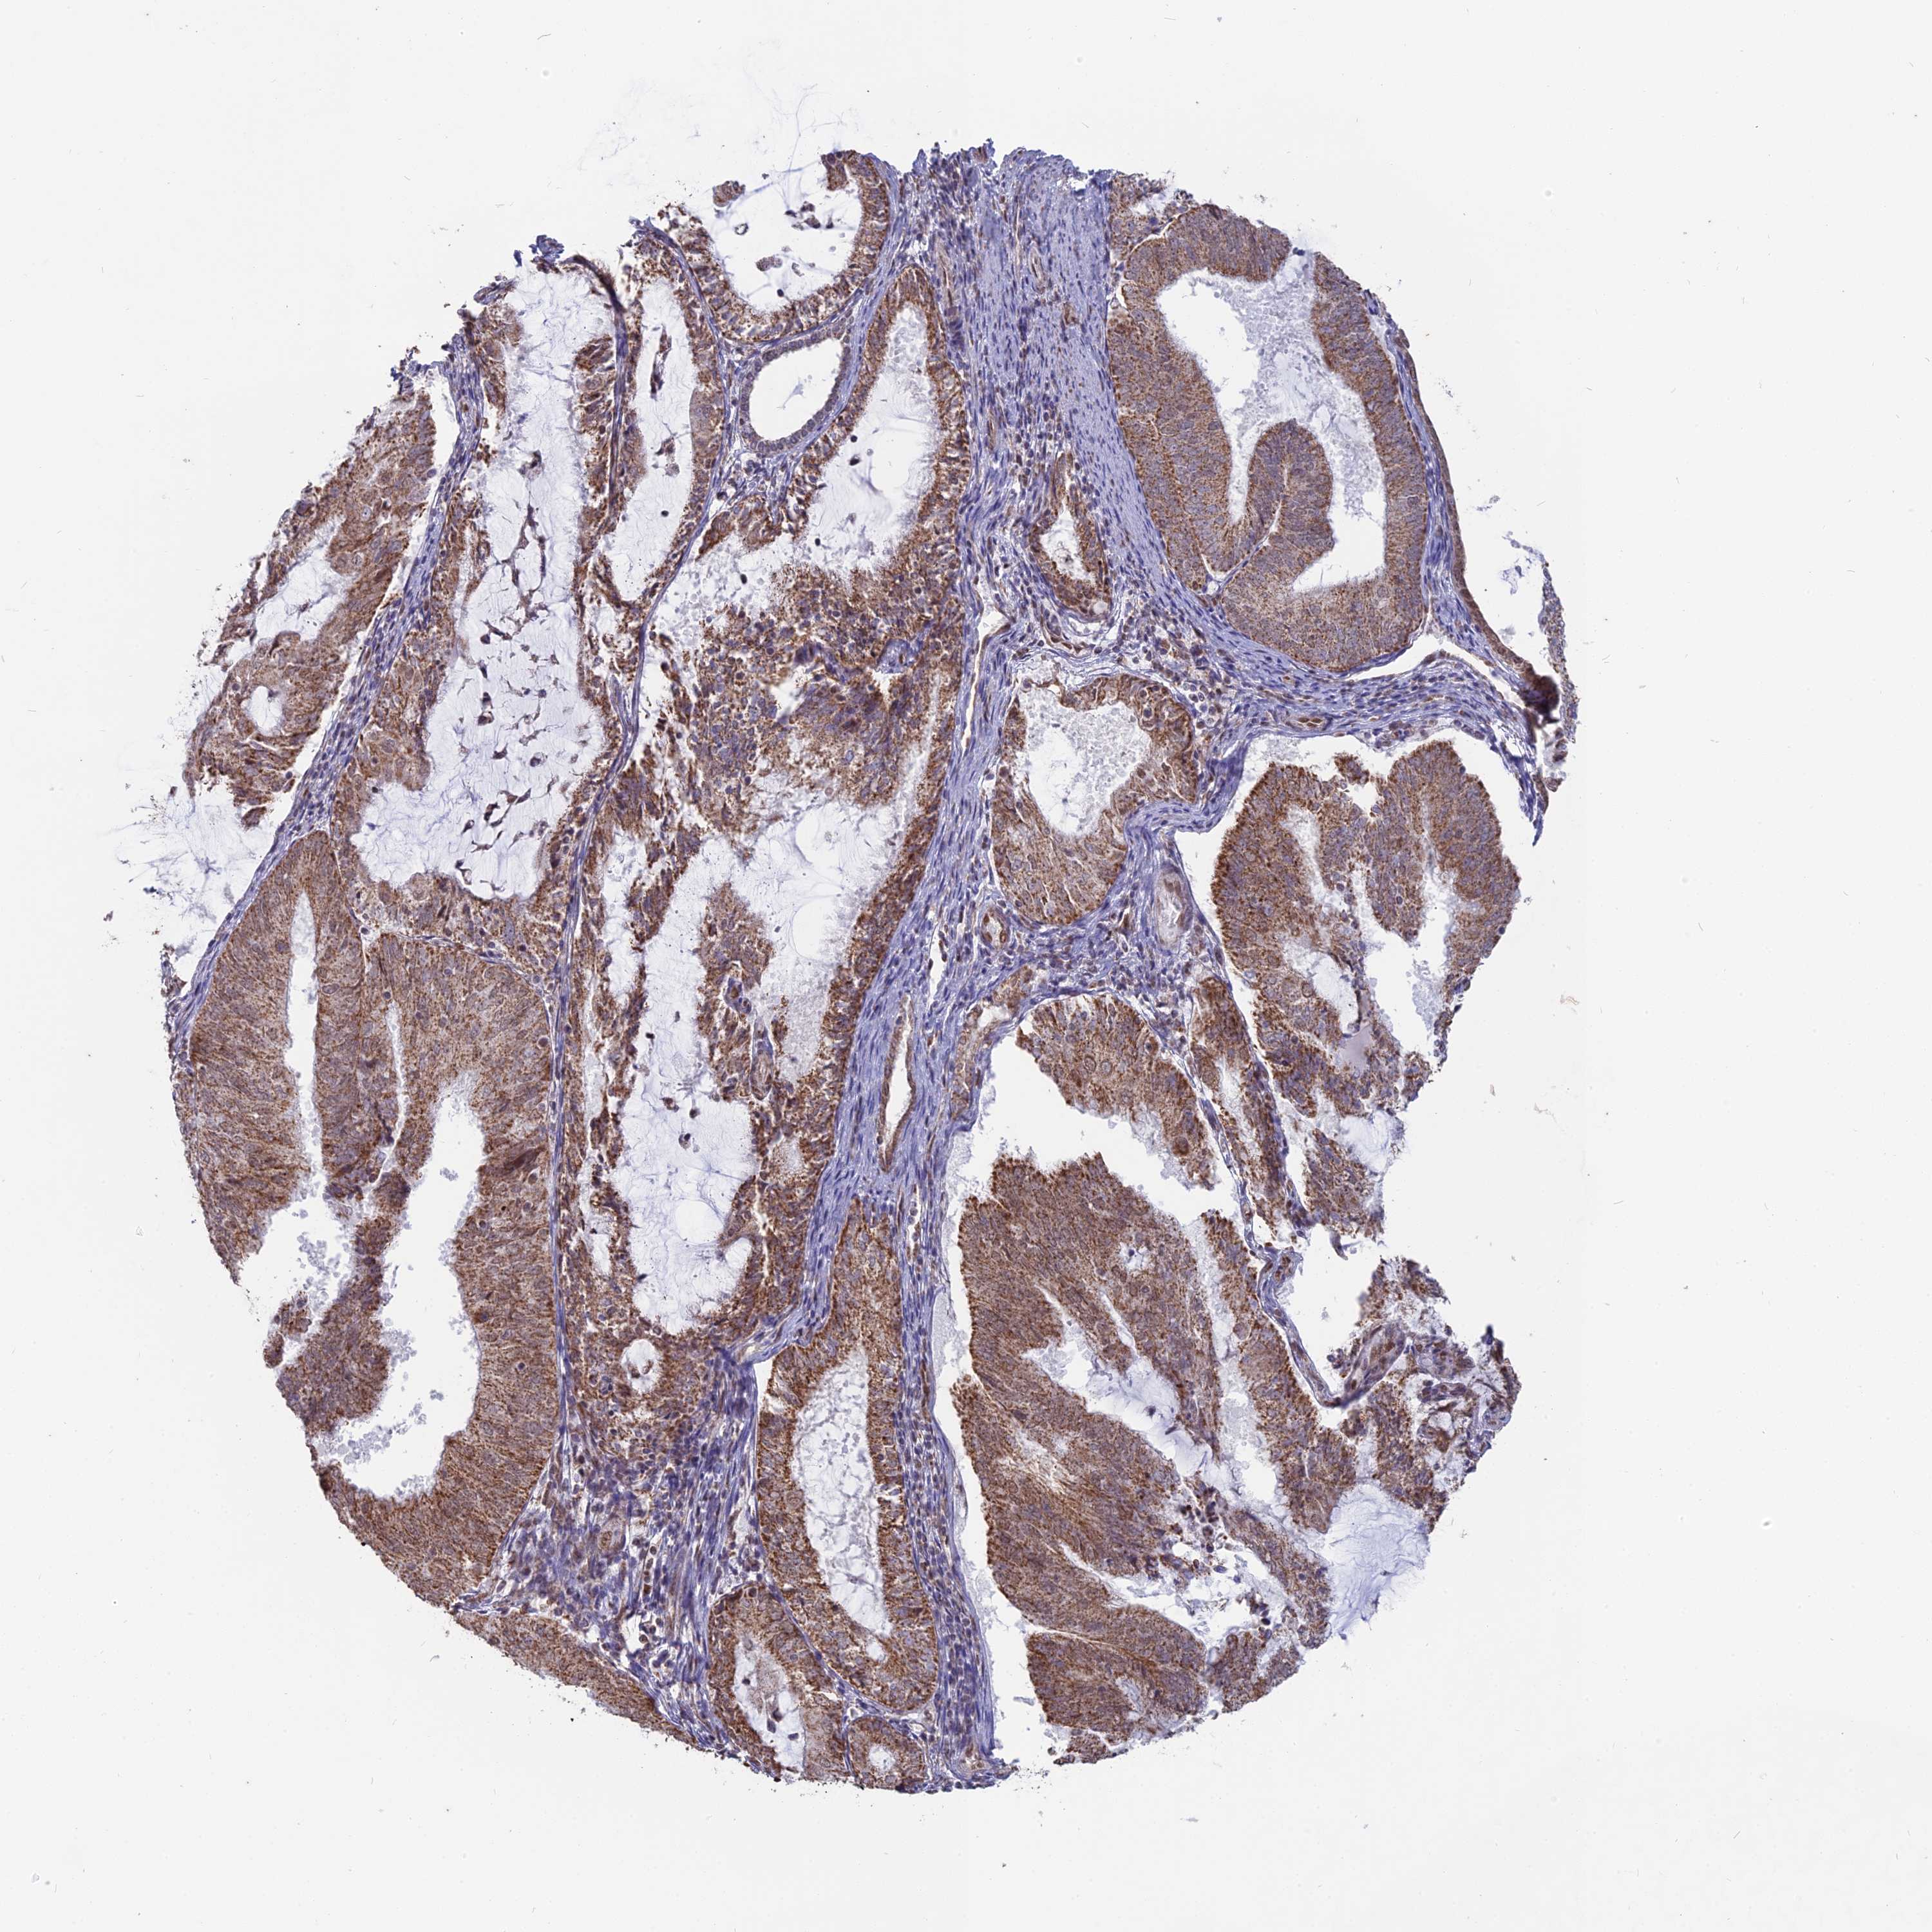

ENDOMETRIAL CANCER - Protein expressioni

A mouse-over function shows sample information and annotation data. Click on an image to view it in a full screen mode. Samples can be filtered based on level of antibody staining by selecting one or several of the following categories: high, medium, low and not detected. The assay and annotation is described here.

Note that samples used for immunohistochemistry by the Human Protein Atlas do not correspond to samples in the TCGA dataset.

Antibody stainingi

Antibody staining in the annotated cell types in the current human tissue is reported as not detected, low, medium, or high, based on conventional immunohistochemistry profiling in selected tissues. This score is based on the combination of the staining intensity and fraction of stained cells.

Each image is clickable and will lead to virtual microscopy that enables deeper exploration of all samples and also displays staining intensity scores, fraction scores and subcellular localization as well as patient and tissue information for each sample.

Antibody HPA042636

Antibody HPA042840

Staining

High

Medium

Low

Not detected

Intensity

Strong

Moderate

Weak

Negative

Quantity

>75%

75%-25%

<25%

None

Location

Nuclear

Cytoplasmic/membranous

Cytoplasmic/membranous,nuclear

Adenocarcinoma, NOS